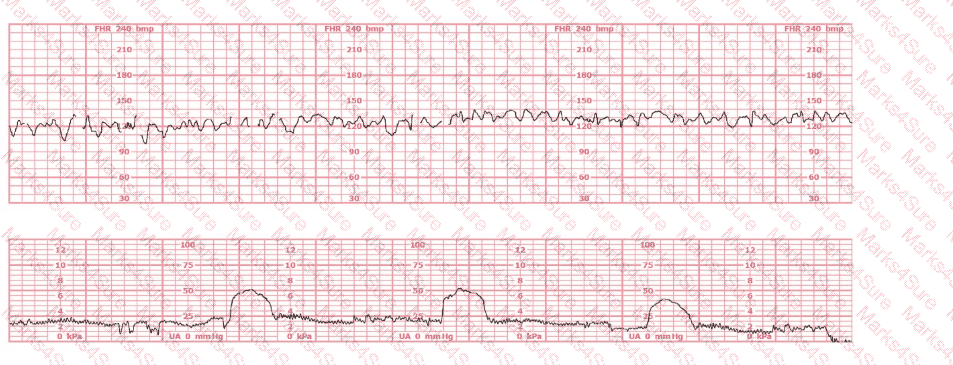

This fetal heart rate tracing is obtained upon the woman's admission to labor and delivery. This tracing is most reflective of: